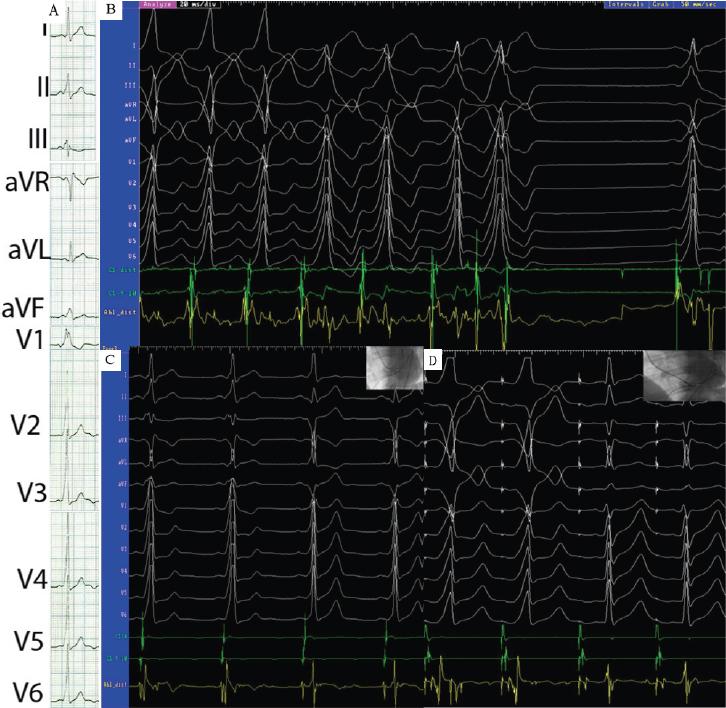

A – 12-lead ECG; B – During catheter manipulation mechanically induced short-coupled atrial extrasystoles unmask two distinct patterns of pre-excitation; C – Initial mapping during SR revealed A-V fusion (first two QRS complexes) on the antero-lateral aspect of mitral annulus (X-Ray LAO projection on top-right corner) and RF application immediately induced A-V split and a sudden change in the pre-excitation pattern (last two QRS complexes); D – Remapping during atrial pacing identified an A-V fusion (first two QRS complexes) on the postero-septal aspect of the mitral annulus (X-Ray LAO projection on top-right corner) and RF application immediately induced an A-V split and sudden loss of pre-excitation (last two QRS complexes); CS, coronary sinus catheter, (9–10 proximal, 3–4 distal); Abl-dist, distal pole of map/ablation catheter.